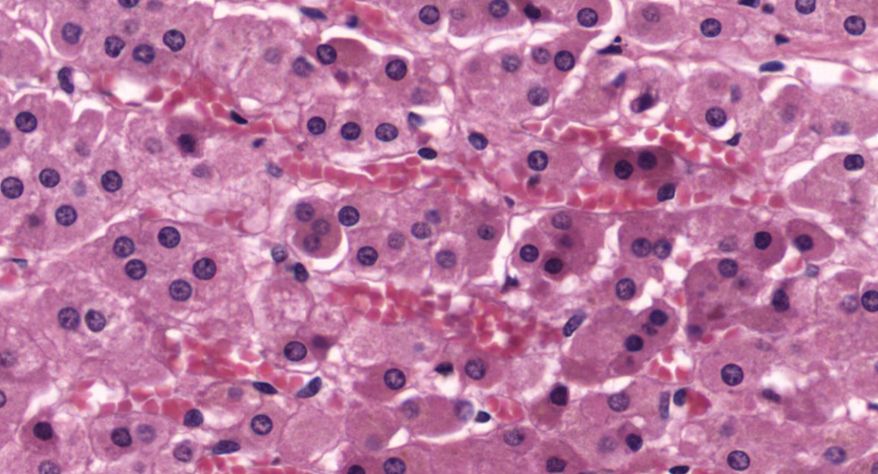

甲状腺

3.滤泡上皮细胞